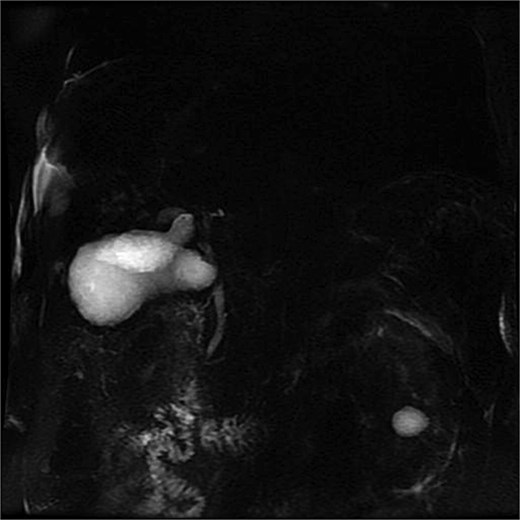

Lab tests showed leukocytosis (15.2 × 103/μl), thrombocytopenia (95.8 × 103/μl), elevated CRP (25.22 mg/dl), procalcitonin (4.49 ng/ml), and total bilirubin (3.5 mg/dl). Liver function was otherwise normal. Ultrasound revealed lithiasic cholecystitis with hydrocholecystosis. Computed tomography (CT) failed to detect duplication (Fig. 1a and b). MRCP confirmed H-type duplicated gallbladder with two independent cystic ducts and mild extrinsic compression of the extrahepatic bile duct (Mirizzi-like pattern) (Figs 2 and 3). MRI sequences (T1 LAVA-Flex and T2 PROPELLER with fat suppression) also demonstrated the duplicated gallbladder and supported the MRCP findings (Fig. 4). No choledocholithiasis was seen.

MRCP showing duplicated gallbladder (H-type), with two independent cystic ducts draining into the common bile duct.